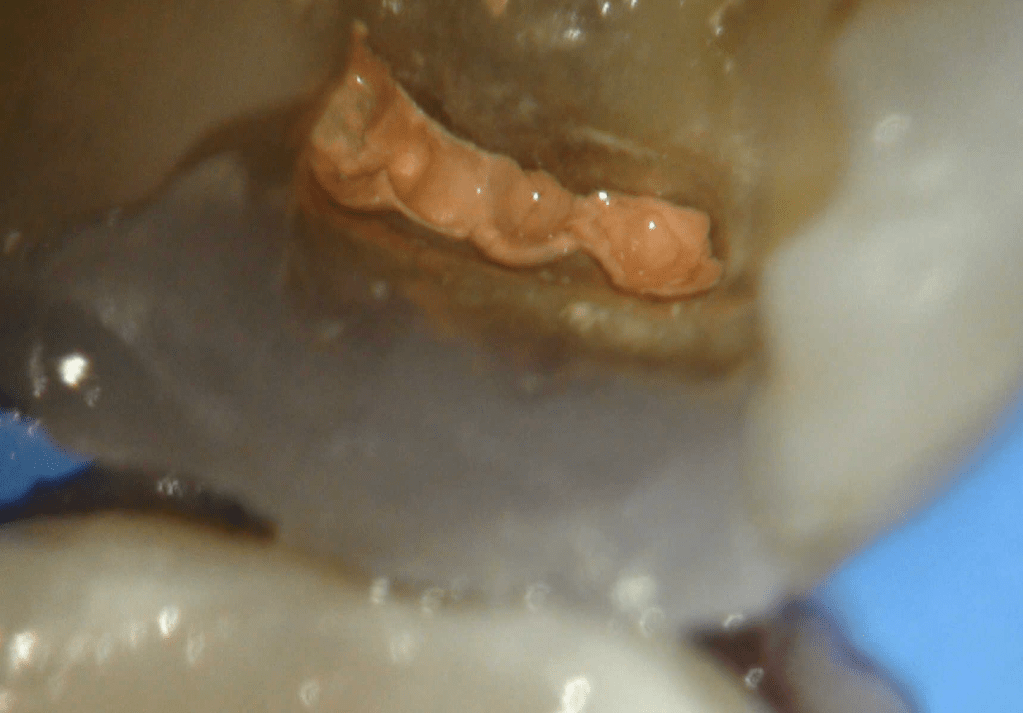

Reconstrucción preendodóntica

Reco pared vesticular

Reco pre-endo, molar inferior

Reco preendo + 4 conductos molar superior

Reco preendo, 2o Molar superior